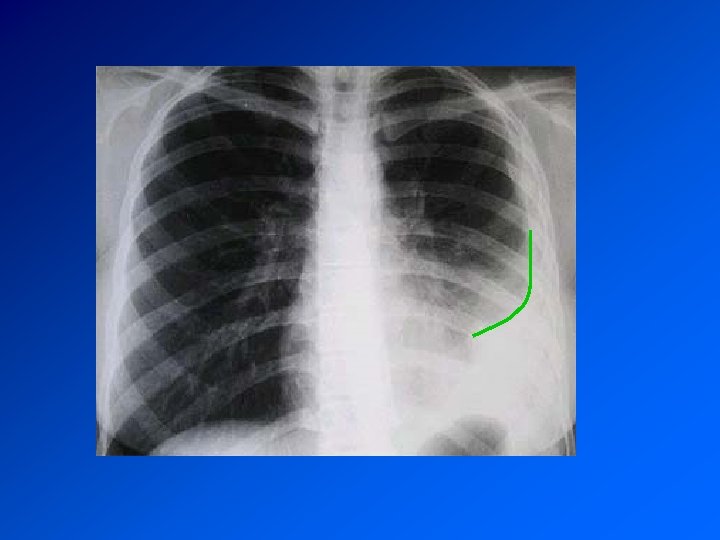

DIAGNOSTIC CDD : Dyspnée, Douleur Autres signes en fonction de l’étiologie Examen : syndrome pleural : matité, abolition de la transmissions des vibrations vocales, abolition du murmure vésiculaire Radio : opacité dense, limitée par une ligne concave en haut et en dedans : la ligne de Damoiseau Bilan biologique : en fonction de l’étiologie

Enquête diagnostique Histoire de la maladie : recherche une maladie déjà connue, une exposition à un toxique professionnel, la prise de médicaments Examen clinique retrouve le syndrome pleural. Recherche de signes d’autres maladies associée Radio de thorax : fait le diagnostic TDM Thorax : précise les images Ponction pleurale oriente en fonction de la cytologie